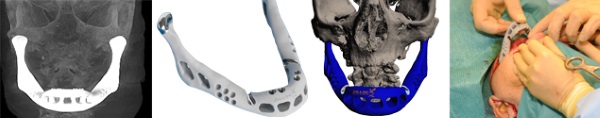

在2012年的時候,比利時和荷蘭(lan) 的科學家為(wei) 一個(ge) 83歲女士成功的更換了一副用鈦金屬3D打印的下頜,這副下頜就是由LayerWise負責製造的。當時是6月份在 Sittard-Geleen的醫院進行的手術,一天後這位女士就已經可以開始說話、吞咽了。LayerWise也因此名聲大振。